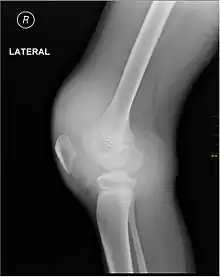

Muscle and joint haemorrhages – or haemarthrosis – are indicative of haemophilia,[7] while digestive tract and cerebral haemorrhages are also germane to other coagulation disorders. Though typically not life-threatening, joint bleeding is one of the most serious symptoms of haemophilia. Repeated bleeds into a joint capsule can cause permanent joint damage and disfigurement resulting in chronic arthritis and disability. Joint damage is not a result of blood in the capsule but rather the healing process. When blood in the joint is broken down by enzymes in the body, the bone in that area is also degraded, this exerts a lot of pain upon the person afflicted with the disease.